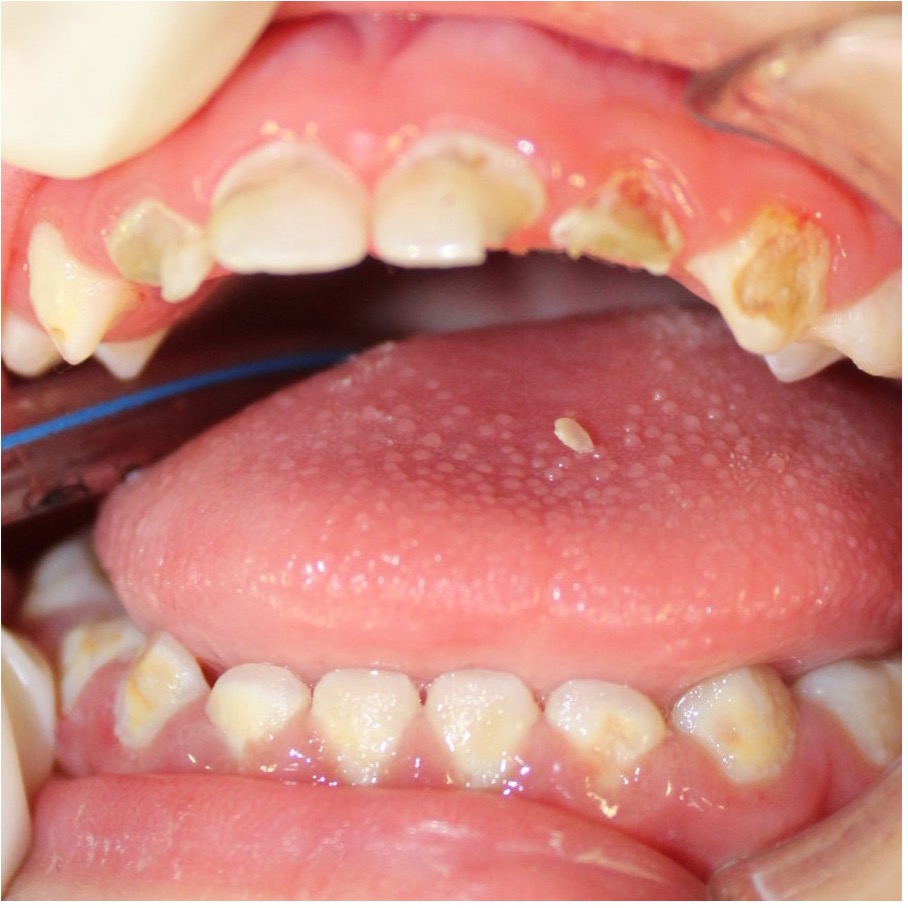

El diagnóstico estomatológico fue: Gingivitis marginal generalizada asociada a placa bacteriana, fracturas dentales post eruptivas de los defectos del esmalte extensión I y II en los dientes 63, 73, 72, 71, 81, 82 y 83 y fracturas post eruptivas de los defectos del esmalte de extensión III de los dientes 62 y 52; además dientes 52 y 62 presentaron pulpitis irreversible. (Figura 1). Oclusión: mordida abierta, caries dental y conducta: comportamiento definitivamente negativo, según Frankl.

Figura 1: Presentación de las secuelas de los defectos del esmalte, fracturas post eruptivas extensiones III en los dientes 62, 52 y fracturas post eruptivas extensión I y II en las piezas 63, 73, 72, 71, 81, 82, 83.